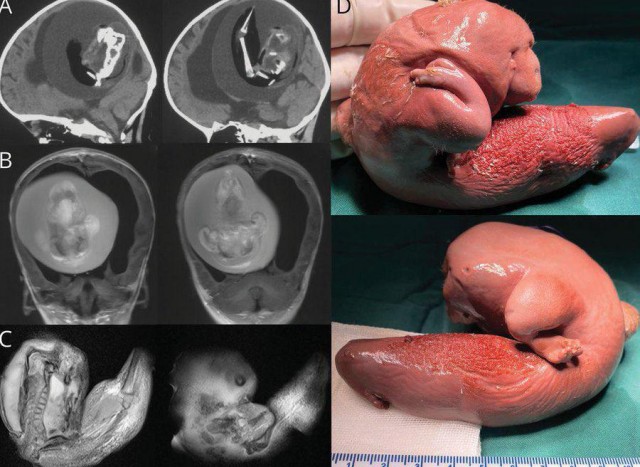

В данном клиническом случае речь идёт о годовалой девочке с задержкой моторного развития; она не могла сидеть самостоятельно. При осмотре окружность головы была увеличена до 56,5 см. Признаков внутричерепной гипертензии (тошноты, рвоты, раздражительности или косоглазия) не наблюдалось. Движения в четырёх конечностях были в полном объёме, мышечный тонус нормальный.

КТ и МРТ головы выявили у новорожденной девочки гидроцефалию, сдавление головного мозга и внутрижелудочковую фетиформную массу. Масса состояла из позвоночника, бедренной и большеберцовой костей. Визуализация показала у плода расщепление позвоночника; при дальнейшем обследовании также были обнаружены верхние конечности и пальцевидные зачатки.

Чужой. Удалено из головы маленький девочки